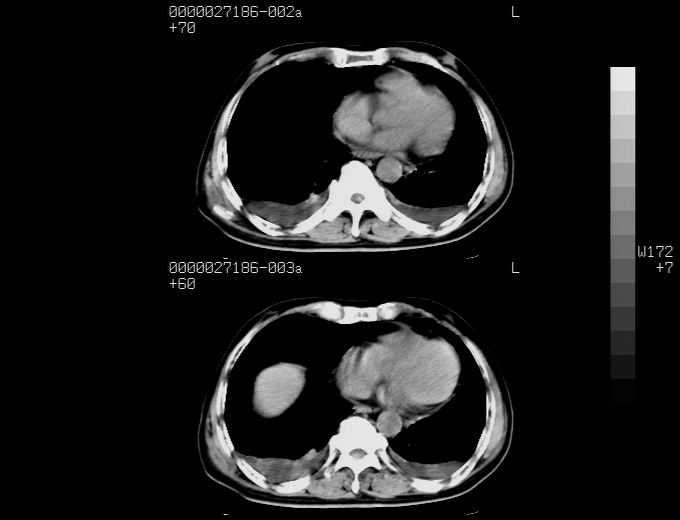

腹胀,腹痛就诊,男性,78岁,外院b超未见异常。

支持脾肾转移瘤,双侧胸腔积液。

考虑弥漫性肝癌并脾及双肾转移.双侧胸水.

肝脾肾转移瘤可能性大,左肾不除外梗塞,双侧胸水

考虑肝癌并双肾及脾脏转移;双侧胸腔积液。